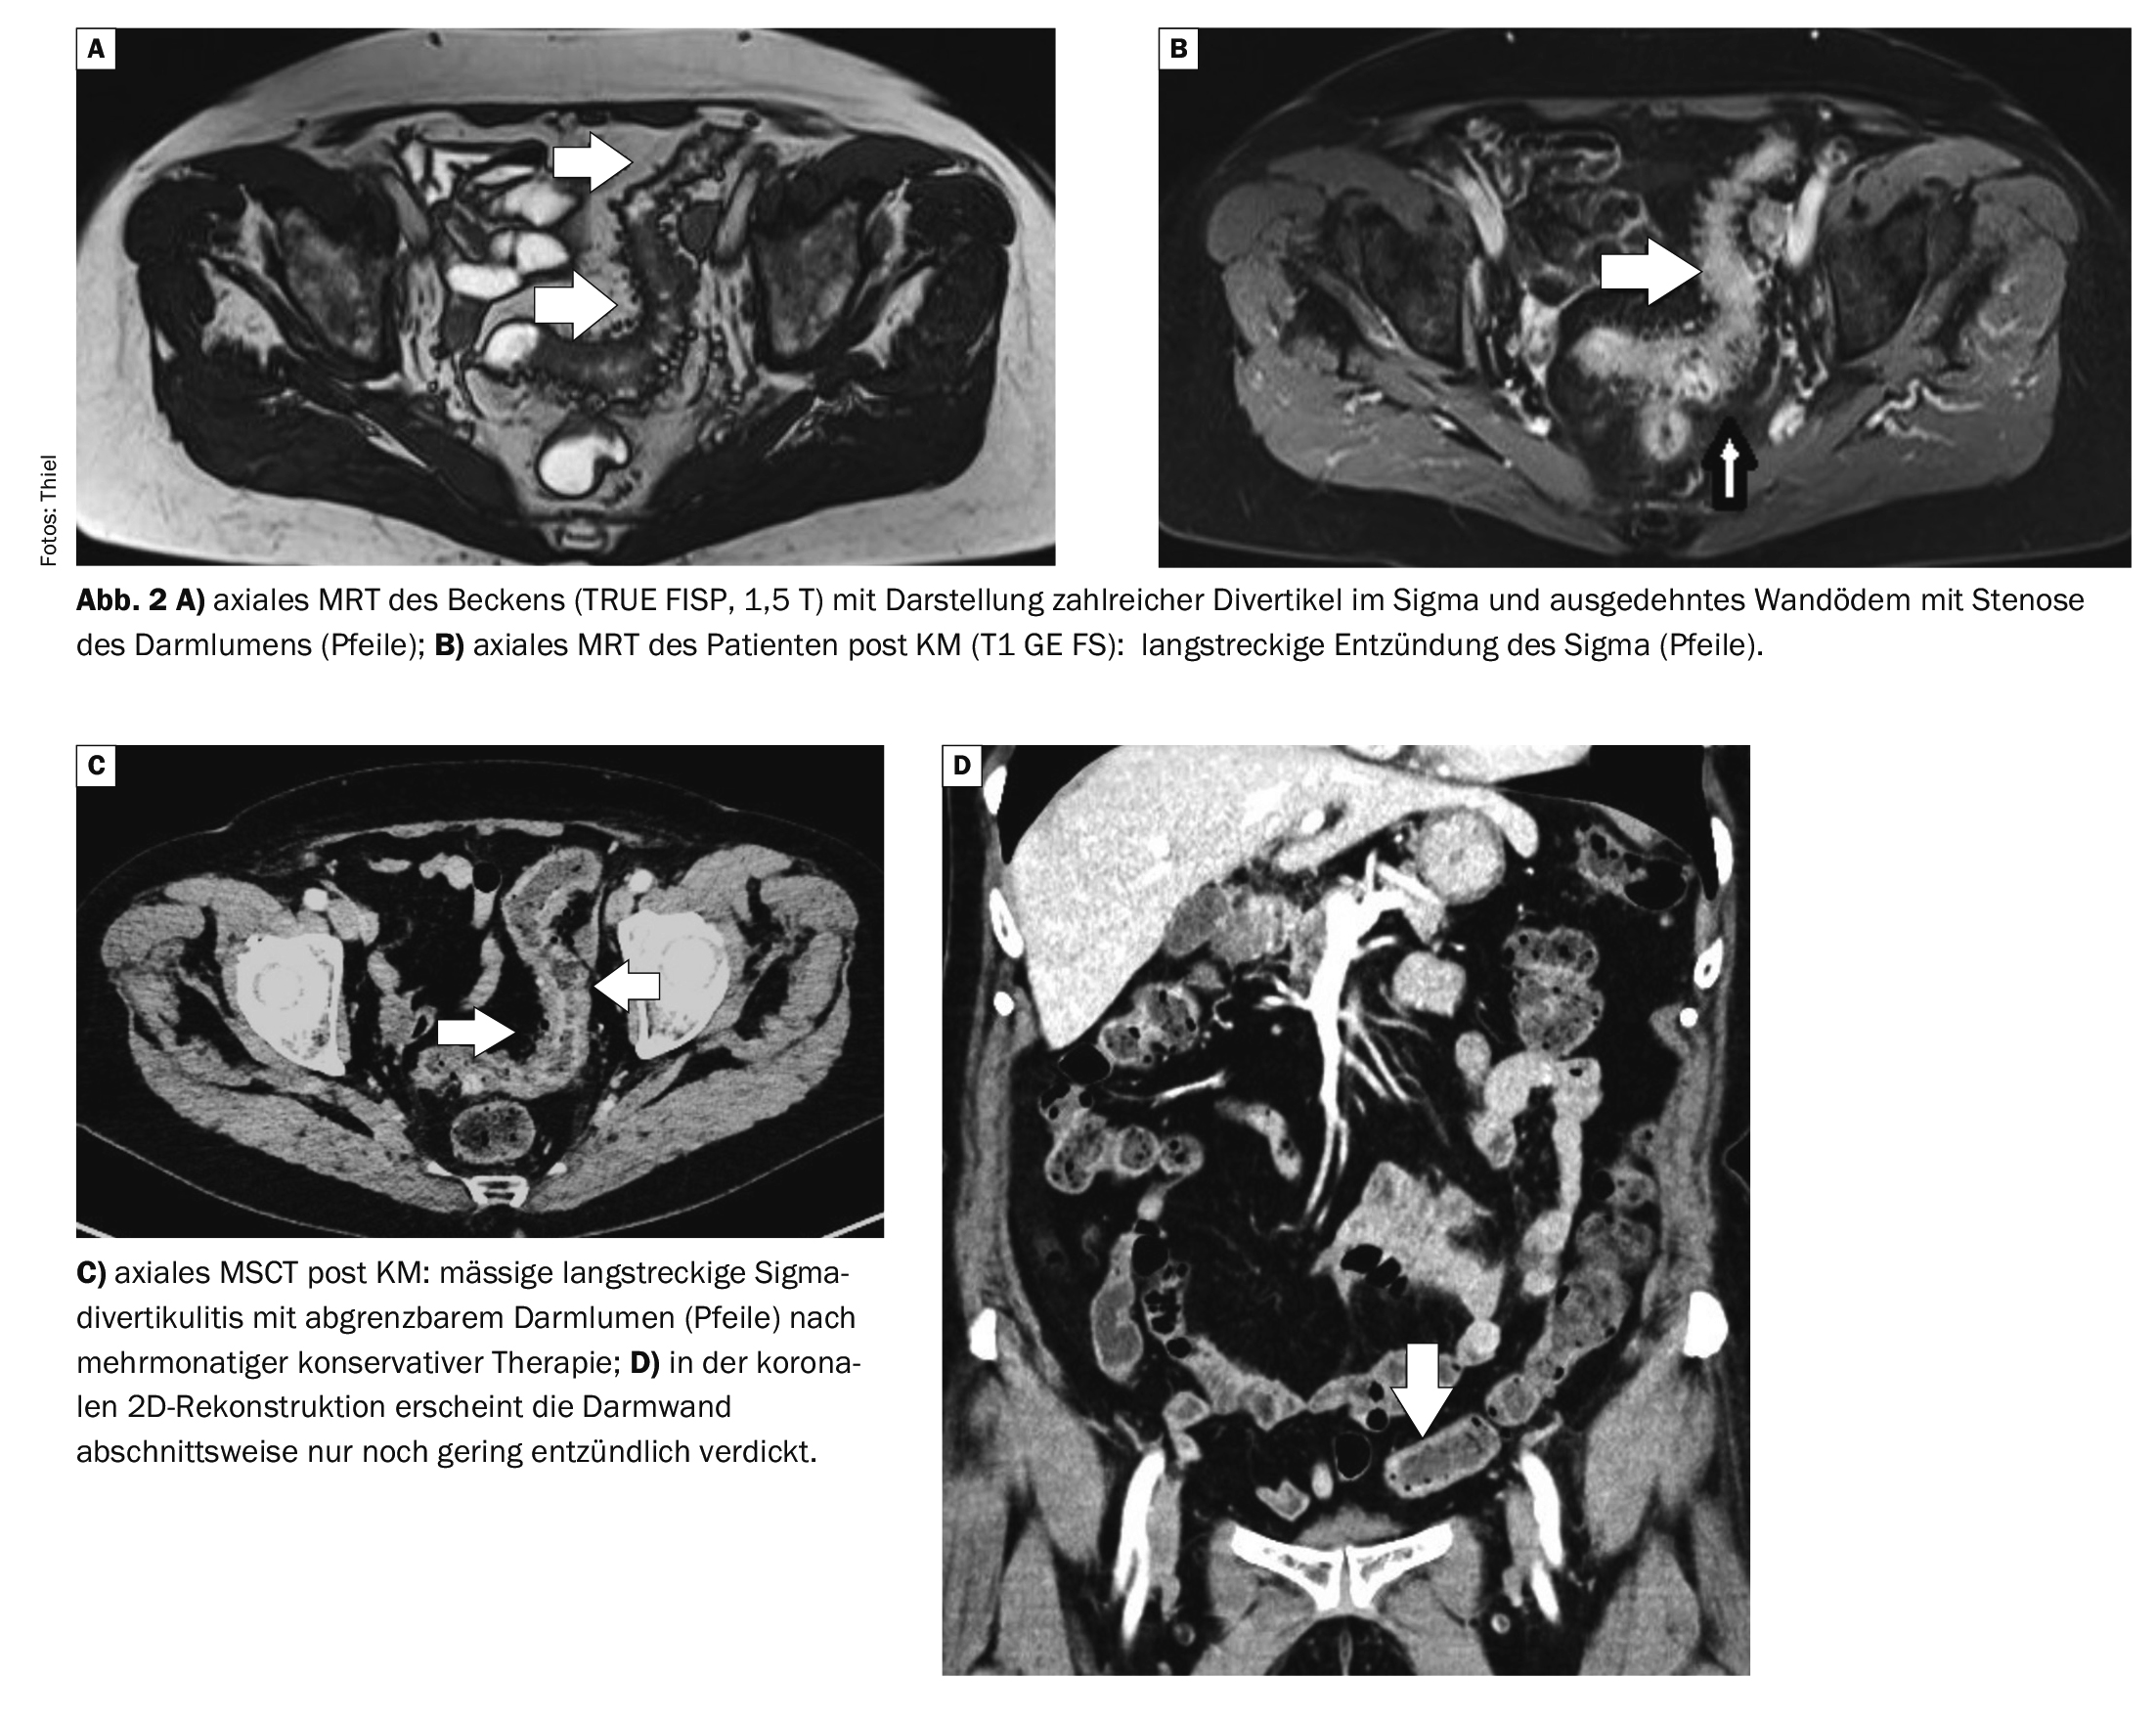

L’IRM est également devenue un outil précieux pour le diagnostic intestinal. Les séquences multiplanaires sans et avec saturation des graisses, ainsi que les séquences assistées par contraste, permettent de détecter avec certitude la diverticulose et la sigmoïdite [6]. Un avantage par rapport au scanner est l’absence d’exposition aux radiations, un inconvénient est la durée plus longue de l’examen et le risque plus élevé d’artefacts, ainsi que la contre-indication des stimulateurs cardiaques, en particulier chez les patients âgés.

Le cas 2 illustre l’évolution d’une diverticulite sigmoïdienne chez une patiente de 70 ans (figures 2A à 2D). L’IRM initiale de l’abdomen montrait une inflammation prolongée du sigmoïde dans le cadre d’une diverticulite étendue, la lumière intestinale étant considérablement sténosée. Lors d’un contrôle après un traitement conservateur intensif, le scanner a montré une amélioration avec encore un gonflement de la paroi, la lumière intestinale était encore modérément sténosée. La formation d’une fistule ou d’un abcès a été exclue.